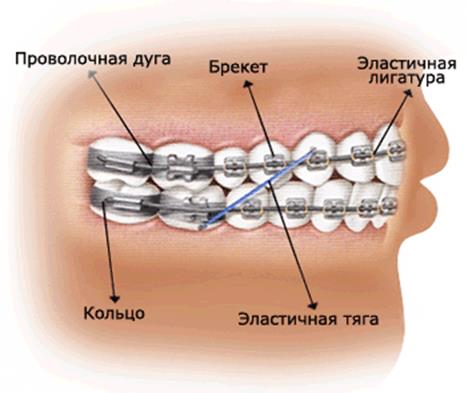

Что такое дуги на брекетах? Зачем они нужны? И зачем их менять?

Как работает брекет-система? Как брекеты выравнивают зубы. Зачем нужно менять дугу у брекетов?

Эластики и чейны в ортодонтии. Зачем нужны межчелюстные тяги на брекетах?